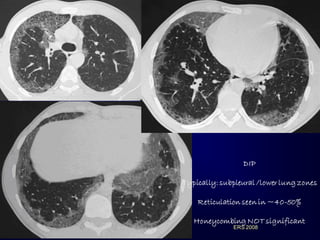

GROUND GLASS: PREVAILING FEATURE ERS2008 GGO in: Outpatients with Slowly Progressive Dyspnea

DIP Typically: subpleural /lowerlung zones Reticulation seen in ~40-50% Honeycombing NOT significant ERS 2008